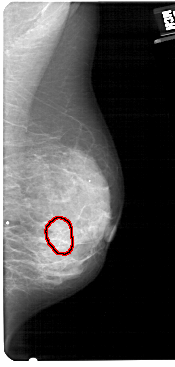

A_1431_1.RIGHT_CC

RIGHT_CC LINES 5026 PIXELS_PER_LINE 2446 BITS_PER_PIXEL 12 RESOLUTION 43.5 OVERLAY

FILE: A_1431_1.RIGHT_CC.OVERLAY

TOTAL_ABNORMALITIES 1

ABNORMALITY 1

LESION_TYPE CALCIFICATION TYPE AMORPHOUS DISTRIBUTION CLUSTERED

ASSESSMENT 4

SUBTLETY 3

PATHOLOGY BENIGN

TOTAL_OUTLINES 1

BOUNDARY